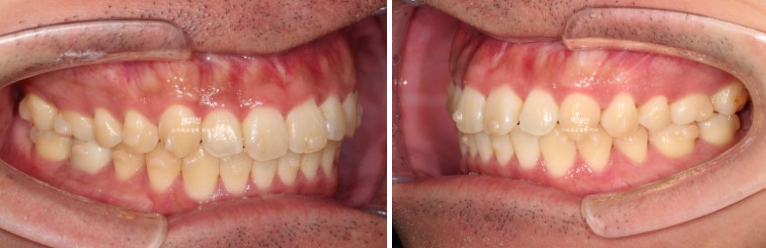

치료 전 후 비교해보겠습니다.

좌 치료 전 / 우 치료 후

24.01~25.05

총 치료기간은 1년 4개월이며 인비절라인으로 치료한 기간은 9개월 입니다.

앞니 돌출의 개선

깔끔해진 미소가 돋보이네요.